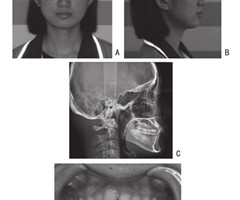

推拉杆推磨牙向后矫治前牙轻度拥挤1例

【关键词】微种植体支抗;磨牙远中移动;螺旋推簧 中图分类号:R783 文献标识码:B 文章编号:1004-4949(2023)23-0180-04 牙列拥挤(crowded dentition)是正畸临床中所见所有错牙合畸形中最为寻常的一种...